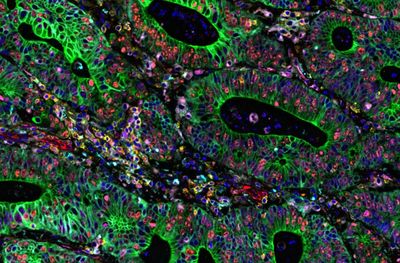

I discovered biological processes that distinguish cancer cell lines based on the aggressiveness of the cancers they model. For both breast cancer and colon cancer cell lines, I calculated, visualized, and functionally annotated differential gene expression profiles with data from the Physical Sciences in Oncology Cell Line Characterization Study.